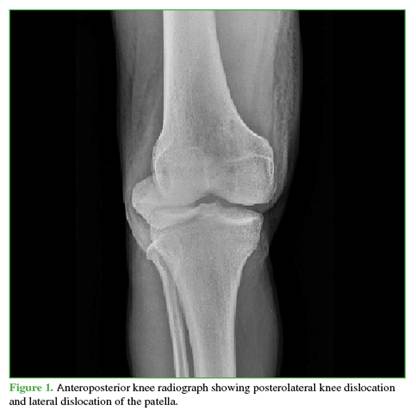

A 27-year-old male farmer residing in a rural area, with no relevant medical history, suffered a traffic accident after falling into a ravine while riding a motorcycle, resulting in trauma to his right shoulder and knee. He initially sought care at a rural hospital, where marked edema, ecchymosis, and a positive dimple sign were identified in the right knee. He also had limited range of motion in both the shoulder and the knee. As X-rays were not available, he was referred to a hospital with orthopedic services. There, initial radiographs were obtained (Figures 1 and 2), documenting a diaphyseal humeral fracture that was immobilized with a sugartong splint. In addition, a posterolateral knee dislocation and a lateral patellar dislocation were diagnosed. Two orthopedic surgeons attempted three reductions under sedation (no anesthesia was available), successfully reducing the patella but not the knee. It was decided that the patient required transfer to a trauma center for urgent open reduction and to rule out an associated vascular injury. The knee was immobilized with a bivalved hip-to-foot splint and he was referred.

Radiographs showed widening of the medial joint space consistent with medial instability. Further imaging was obtained with magnetic resonance imaging (Figures 4 and 5) to evaluate possible interposed tissues or structures, and with CT angiography (Figure 6) to rule out vascular injury given the time elapsed since trauma. Marked edema was noted in the medial soft tissues, including the capsule and medial structures in the intercondylar region, along with persistent knee subluxation. Vascular compromise was ruled out, with preservation of the femoropopliteal vascular bundle.